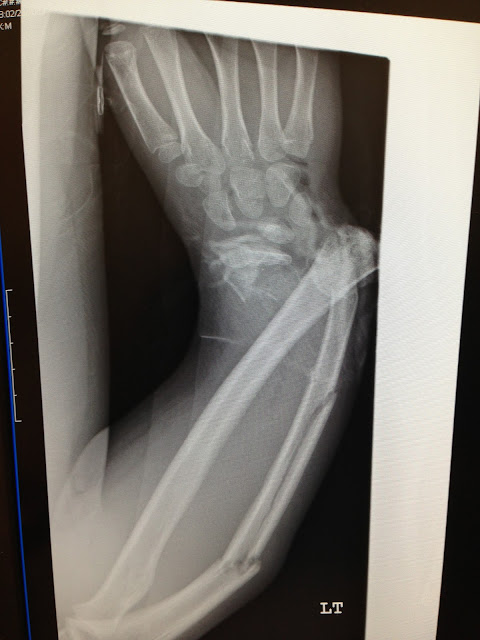

Sometimes a wrist injury is obvious, and there are broken bones seen on an x-ray, such as in these examples:

Again, those are pretty obvious examples, and you certainly wouldn't need to be a radiologist to see that there's a problem.